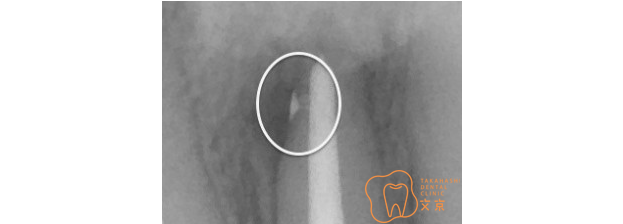

■根管治療は歯の寿命を左右する

■前歯が折れてしまった、、、